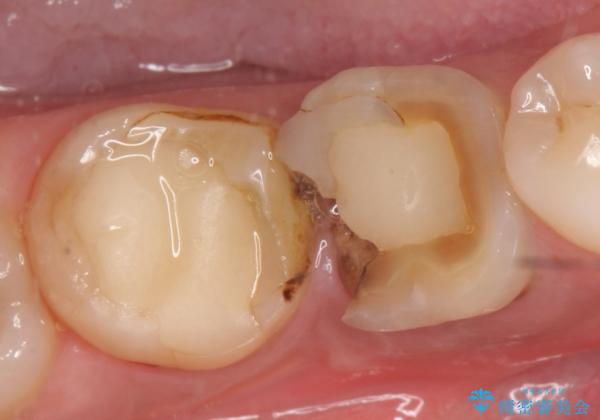

オールセラミッククラウン 欠けてしまった奥歯の治療

- 奥歯が欠けてしまったので診て欲しいといらっしゃった方の症例です。

再根管治療終了後、オールセラミッククラウンによる補綴を行いました。

今回用いたオールセラミッククラウンはジルコニアフレームという白い素材の上にセラミックを盛っているため、審美性が非常に高いのが特徴です。

また、ジルコニアは人工ダイヤモンドの材料にも使われているほど高い強度を持っており、そのためオールセラミッククラウンは審美性だけでなく、奥歯やブリッジの補綴も可能とするクラウンです。